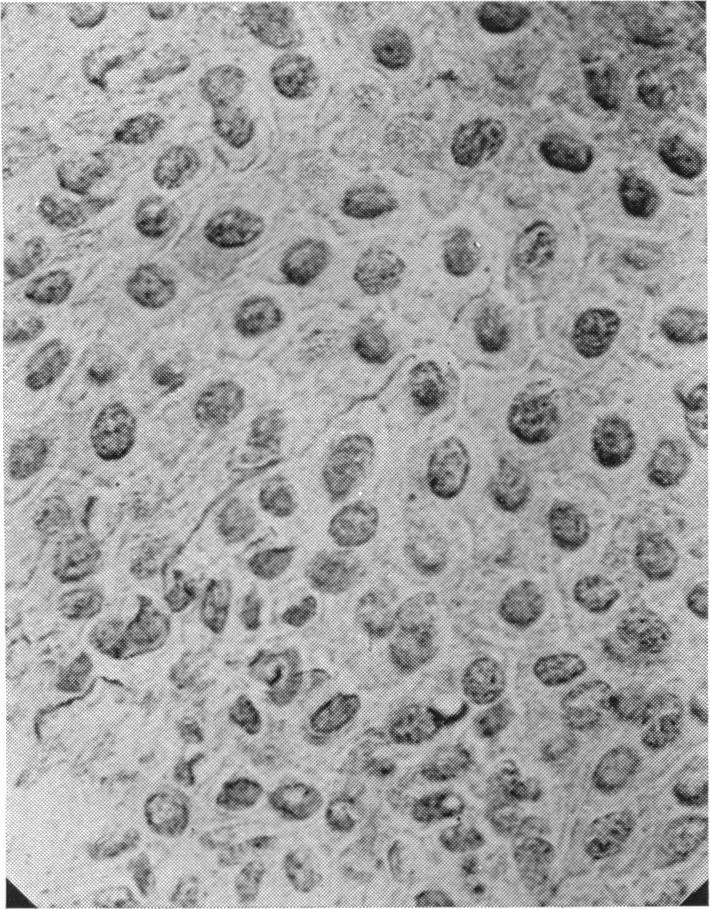

The Innervation of the Human Gum.

J Anat. 1938 Jul;72(Pt 4):531-534.3.